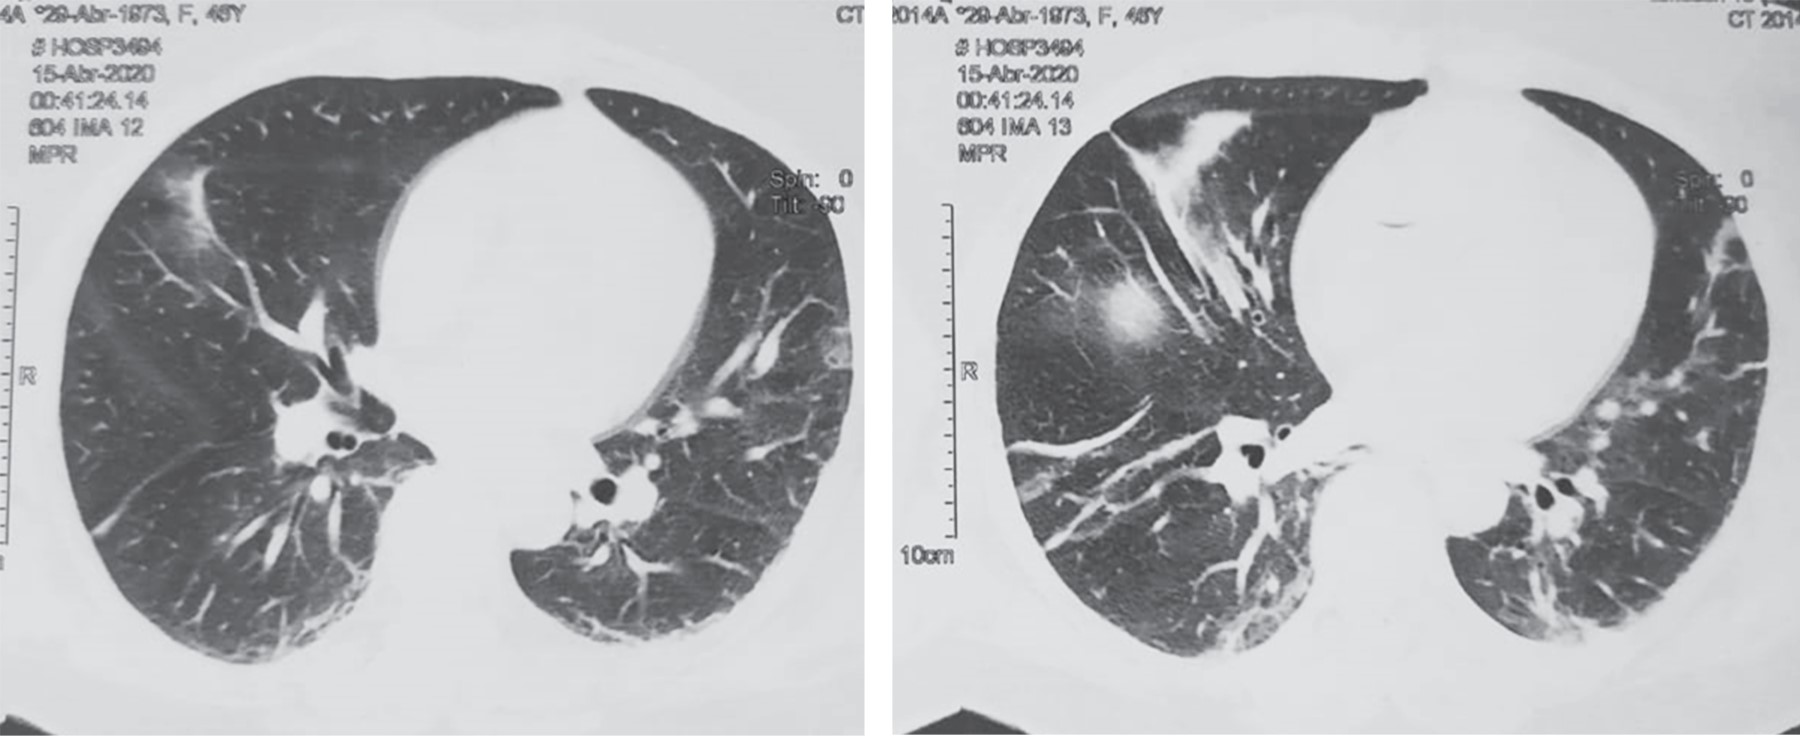

This is the case of a 47-year-old female patient with no relevant medical history. She smoked 20 cigarettes per day with a smoking index of 25, which is considered as a major risk for chronic obstructive pulmonary disease (COPD); she had an elective cesarean section 13 years ago. Her condition began four days prior to her evaluation, when she presented pain in the epigastrium of intensity 7/10 without irradiation, without triggering or exacerbating factors; it was accompanied by nausea and vomiting of food content on five occasions. Twenty-four hours after the onset of the symptoms, she reported having self-medicated with the antispasmodic drug butyl-hyoscine 10 mg every 12 hours, after which she had a slight improvement, so she was left to free evolution. 48 hours later she presented increased vomiting, as well as abdominal pain that had migrated to the right iliac fossa. She did not report having fever. She went to a private hospital 72 hours after the onset of the symptoms, where amikacin as antibiotic was administered along with an analgesic drug and metoclopramide at unspecified doses, without relieving the symptoms. At another private hospital where she was taken because of increasing intensity of abdominal pain, laboratory studies were performed that showed: a white blood cell count of 23.3 × 103/μl with a neutrophil count of (19.48 × 103/μl). The rest of the laboratory parameters were within normal range values. Once acute appendicitis was suspected, a contrasted thoraco-abdominal-pelvic CT scan was requested, which showed signs of a probable acute appendicitis complicated with a localized abscess, as well as findings of air bronchogram and data suggestive of atypical pneumonia due to SARS-CoV-2 (Figures 1 and 2), so it was decided to send her to the emergency department of our hospital unit.

Figure 1